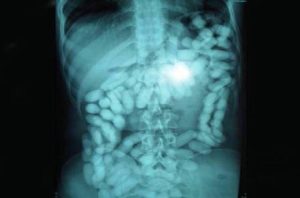

Con dicha información, ambos fueron llevados al Hospital Central de San Cristóbal; donde les realizaron pruebas de rayos X que confirmaron la presencia de cuerpos extraños en su marco colónico. En tal sentido, estuvieron bajo estricta vigilancia médica hasta que Caicedo Carreño expulsó 78 dediles de cocaína cuyo peso neto de un kilo con 243 gramos. Por su parte, Guerra Acosta expulsó 40 dediles con peso de 510 de gramos de la misma sustancia.